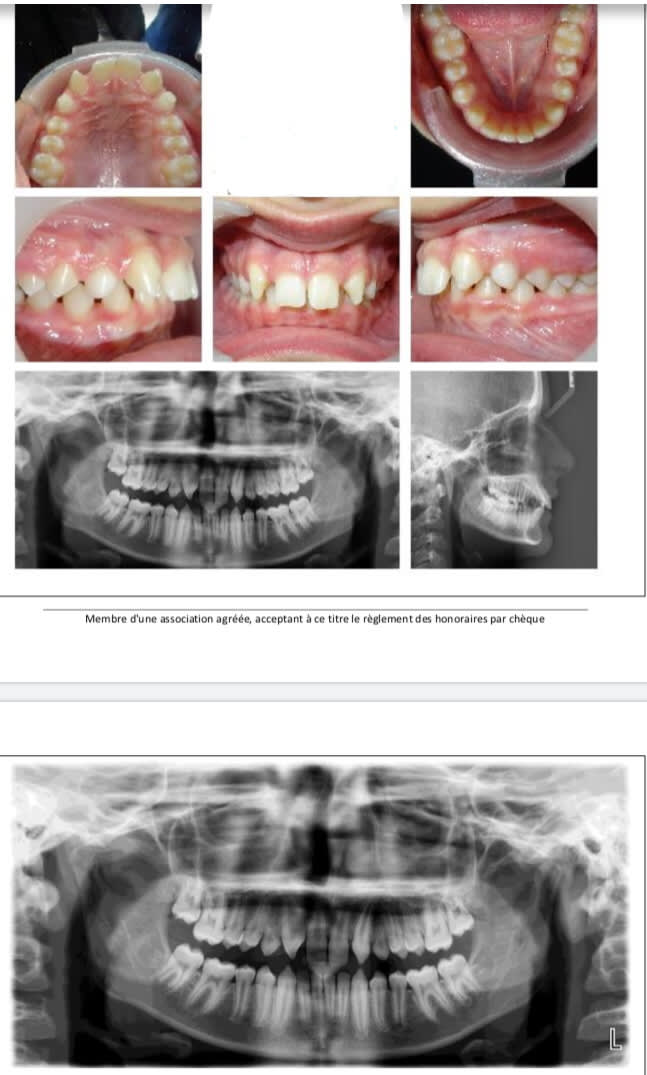

Un nouveau cas adresse, jeune garçon de 12 ans et 6 mois avec agénésie de 12 et 22

Alors, l’orthodontiste va gentiment me reculer 13 et 23 mais :

- à quel âge implanter ?

- quelle solution transitoire?